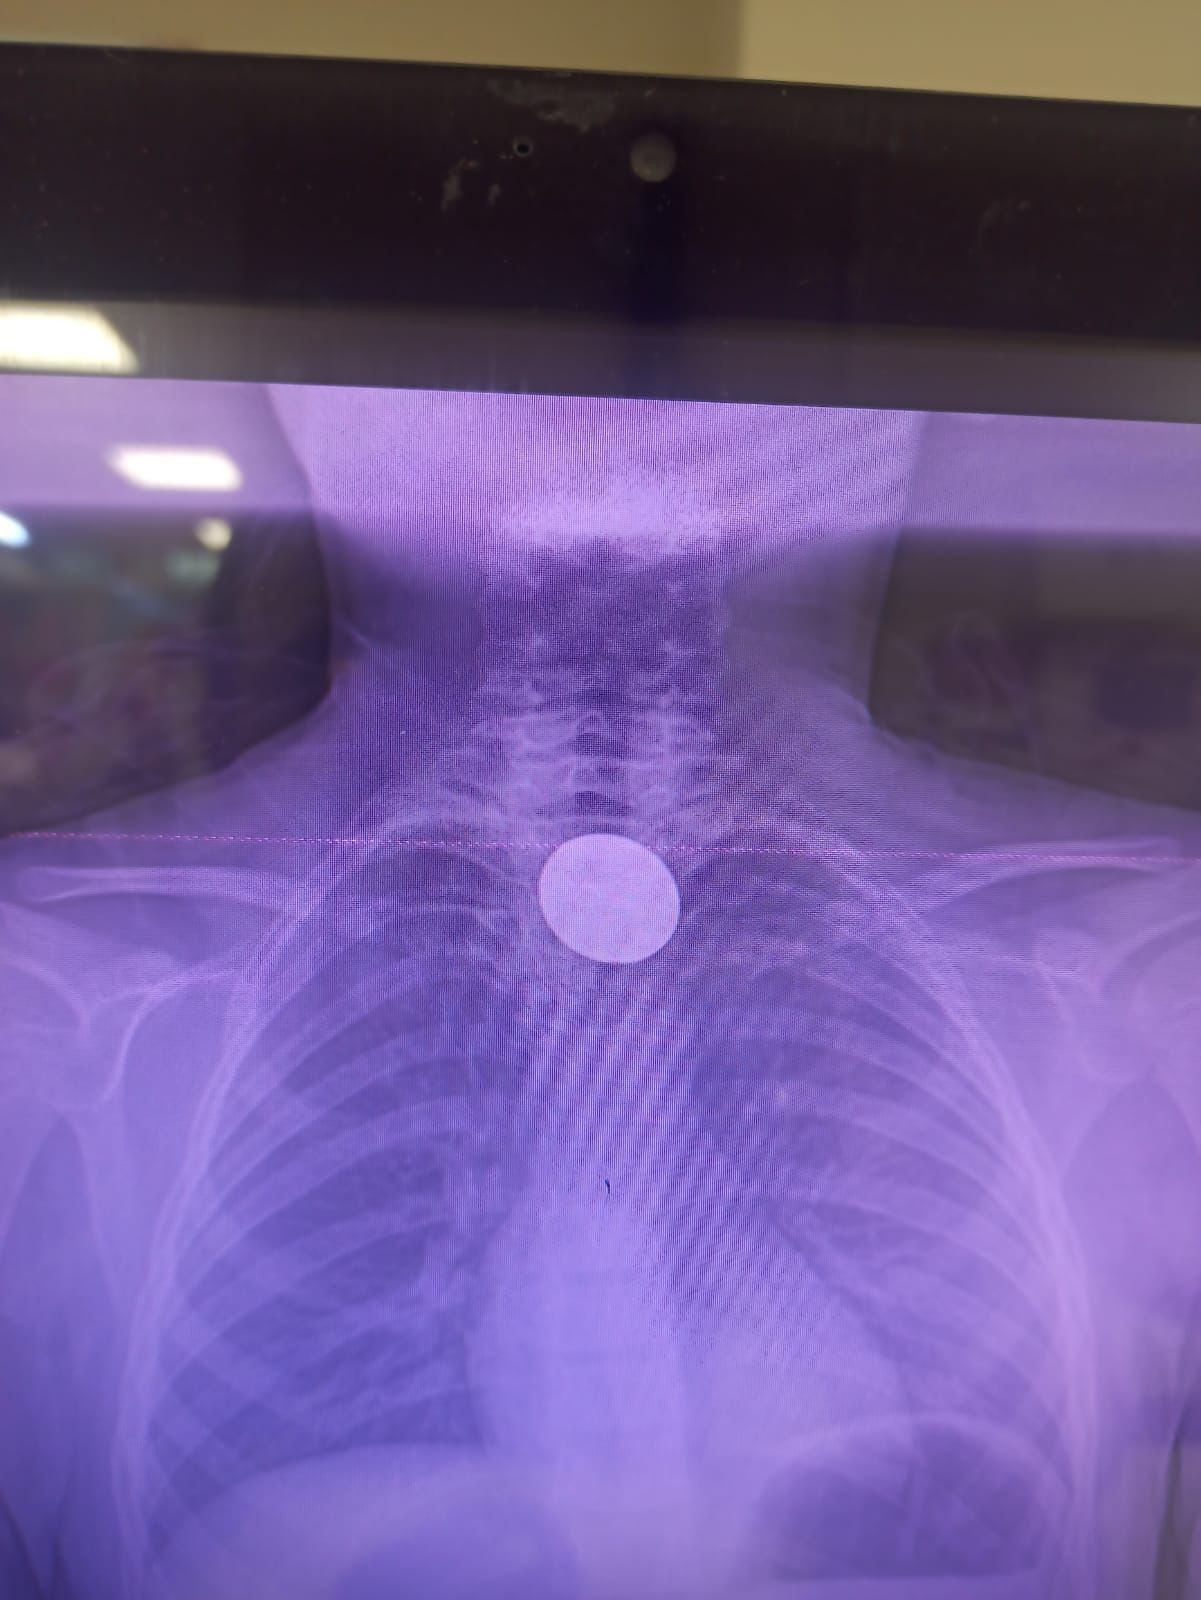

Yabancı cisim yutma şikayetiyle ailesi tarafından Siirt Eğitim ve Araştırma Hastanesine getirilen 8 yaşındaki Y.K.'ya yapılan ilk değerlendirme ve görüntüleme tetkiklerinin ardından ilgili branşlar tarafından operasyona alındı. Y.K.'nın yemek borusuna kadar ilerlediği tespit edilen madeni para, Gastroenteroloji Uzmanı Dr. Yaren Dirik ve Kulak Burun Boğaz (KBB) Hekimi Dr. Yasin Gökçınar tarafından endoskopik yöntemle çıkartıldı.

"Görüntülemeyle, hastanın hikayesi ve ailesinin 5 lira yuttuğunu söylemesi üzerine tetkiklerini değerlendirip ameliyata aldık. Bu süre zarfında hastamız aç bekledi, her hangi bir şey yiyip içmedi. Bu, önemli. Herhangi bir yabacı cisim yutma, soluk borusuna kaçması durumunda önemli bir durum. Acil hava yolu durumu gelişebilir. Hava yolu tıkanması durumunda direkt solunum sıkıntısı oluşabiliyor ve hasta hayatını kaybedebiliyor. Çocuklarımızın yabancı cisimlerle oynamasına çok aşırı müsade etmemekte fayda var. Çocuk, şanslı bir çocuk. Çünkü soluk borusu yerine mutak borusuna girmiş bir para. Soluk borusuna gitseydi hayatını kaybedebilirdi. Mideye gitmeden hocamızın da desteğiyle çıkartmış olduk. Hastamız taburcu oldu, gayet iyi durumda."

"Yaptığınız ön tetkiklerde kulak burun boğazla birlikte değerlendirdiğimizde paranın yemek borusuyla ağız tabanı arasında, KBB'nin hem de gastroenteolojinin ortak girişiyle yapabileceği bir alanda olduğunu tespit ettik. Tespitten sonra KBB ile istişarede bulunduk. Ortaklaşa işleme aldık ve madeni 5 lirayı ameliyatsız bir şekilde endoskopik olarak çıkardık"